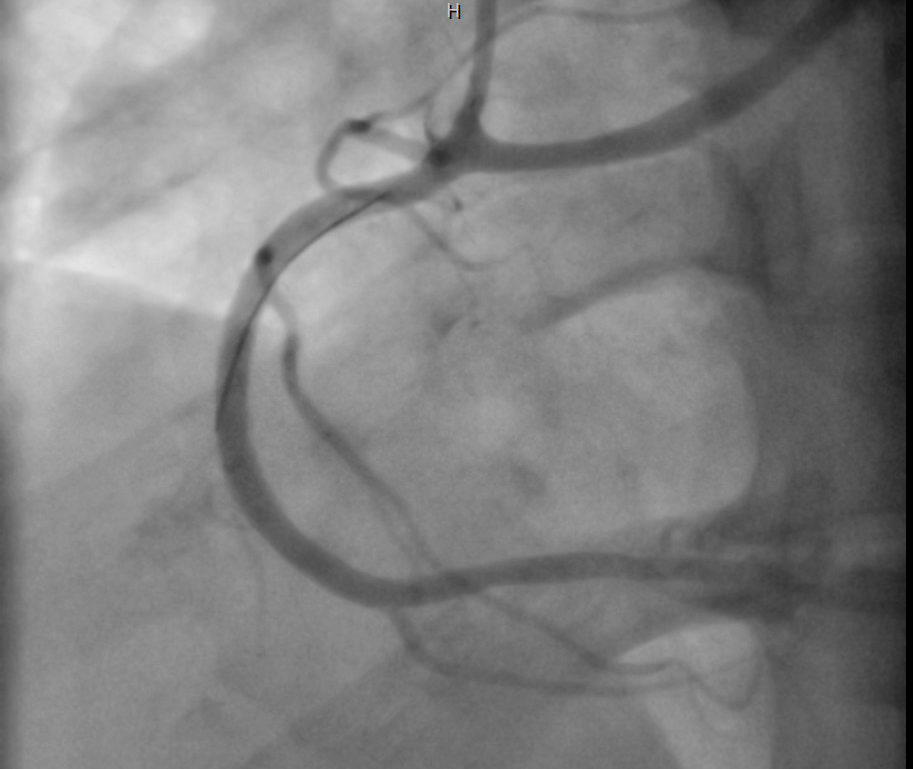

Coronary angiography was performed through right radial approach using 5F TIG catheter. Left coronary sinus contrast injection failed to show any coronary artery origin despite multiple attempts. Right coronary sinus injection showed a coronary artery arising from right coronary cusp as a single trunk which divides into RCA and left system. Left system further divides into LAD and LCX. Mid RCA showed a very tight concentric severe stenosis. Left system was devoid of any significant disease.

Percutaneous Coronary Intervention (PCI) of mid RCA: Common coronary trunk ostium was engaged with a 6F JR4.0 guiding catheter with meticulous care to prevent any ostial injury. Mid RCA lesion crossed with a 0.014¡± BMW wire. Predilated the lesion with 2.5x12mm semi compliant balloon. Stenting of the lesion was done using a DES (3.5x23mm) with final good result. A cardiac CT was done following PCI which confirmed the angiographic findings and found normal subpulmonic non-malignant course of left branch vessel (Lipton's class R II A).